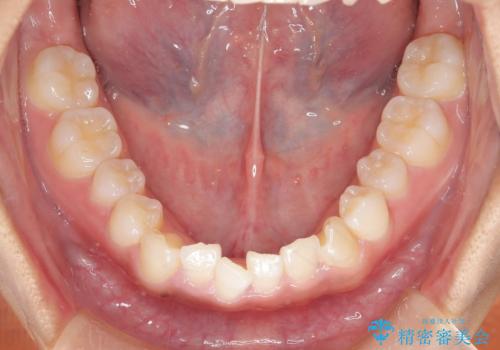

- 前歯の叢生(がたつき)を主訴に来院された患者様です。以前マウスピース矯正をされていたそうでしたが、自身での継続が難しいことなどを理由に、ワイヤー矯正にて改めて矯正治療を希望されました。非抜歯にて治療を計画し治療を行いました。

歯の動きが良く、スムーズに治療を終了しました。一般的にワイヤー矯正はブラッシングが難しいのですが、毎回一生懸命セルフケアをされていたのが印象的です。治療においては、歯の衛生状態も一緒にチェック致します。